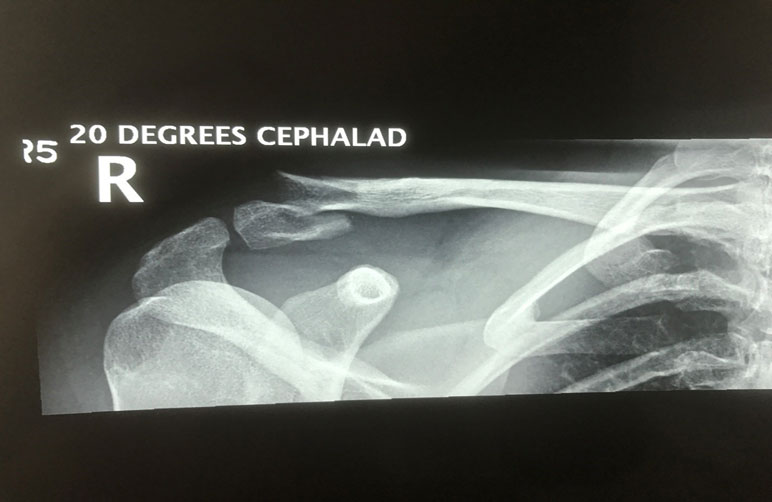

What do clavicle fractures look like on X-ray?

Below are examples of typical fractures that benefit from surgery.

Click an image to enlarge